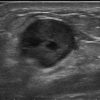

Ung thư vú

Ung thư vú - Ảnh 3

» Thông tin: Nữ giới – 54 tuổi.

» Lâm sàng: Khối tuyến vú.